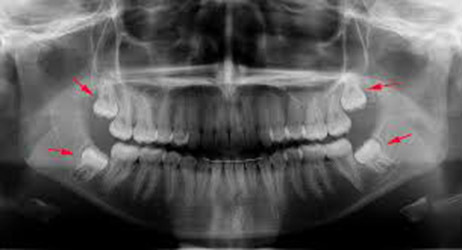

4_partes_corpo_desnecessarias_11. Dentes do Siso

Os sisos são os últimos dentes da boca, aqueles que geralmente nascem quando estamos a dar entrada na vida adulta. Muitas vezes é necessário realizar uma cirurgia para retirá-los, pois podem atrapalhar a estrutura dos outros dentes e/ou causar infecções. Para os nossos antepassados o siso era útil porque facilitava a mastigação. Mas como hoje em dia não precisamos mais de uma arcada dentária forte para mastigar raízes, folhas, morder ossos e arrancar carne, o siso só serve mesmo para dar dores de cabeça, e de dentes.